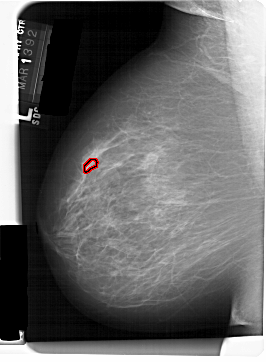

A_1466_1.LEFT_CC

LEFT_CC LINES 6871 PIXELS_PER_LINE 4666 BITS_PER_PIXEL 12 RESOLUTION 43.5 OVERLAY

FILE: A_1466_1.LEFT_CC.OVERLAY

TOTAL_ABNORMALITIES 1

ABNORMALITY 1

LESION_TYPE CALCIFICATION TYPE PLEOMORPHIC DISTRIBUTION CLUSTERED

ASSESSMENT 4

SUBTLETY 2

PATHOLOGY MALIGNANT

TOTAL_OUTLINES 1

BOUNDARY